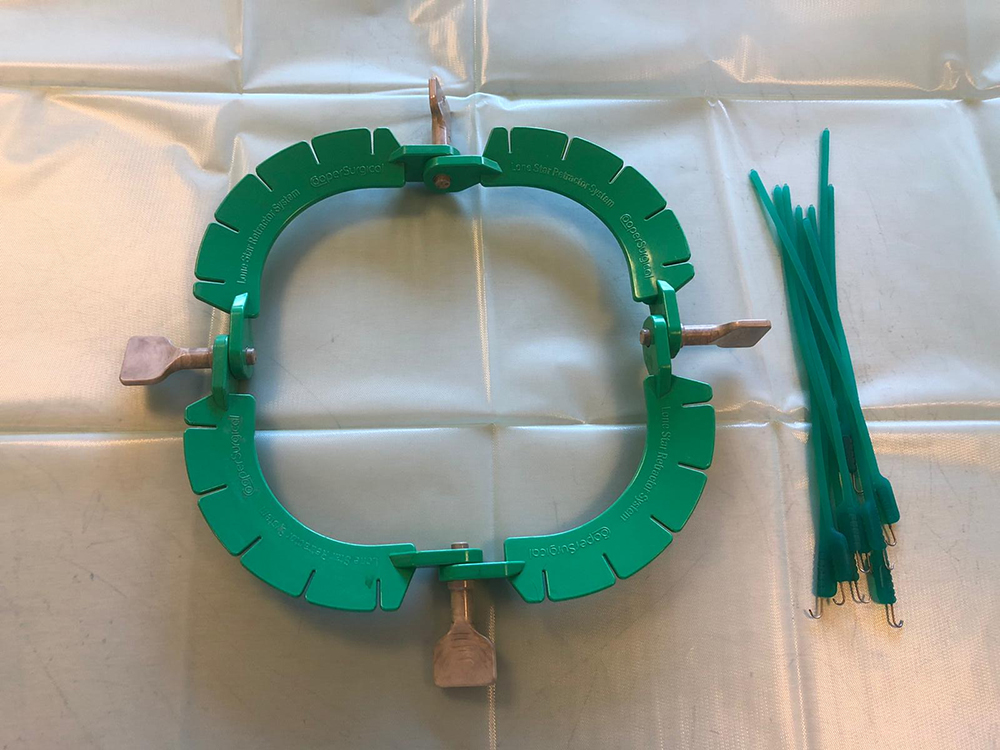

Nu kan de buik geopend worden, tot vlak voor het bekken. Om de buik open te houden, wordt de “lone star retractor” geplaatst. Hiermee is er goed zicht en werkruimte te verkrijgen. De eierstokken liggen bij het konijn vrij ver naar de zijkant, de darmen liggen vaak in de weg en zijn erg fragiel. Met de “lone star retractor” kan de sterilisatie veiliger worden uitgevoerd.